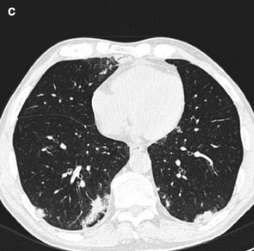

Important

Among febrile neutropenic patients with a “normal” chest X-ray, up to 60% may have findings of pneumonia on CT scanning.

Figure 18: Normal chest X-ray in a neutropenic patient with occult pneumonia

Figure 19: CT scan revealing pulmonary infiltrates not visible on chest X-ray

Common CT Findings in Neutropenic Pneumonia

Figure 20: CT imaging patterns and their differential diagnosis in neutropenic patients